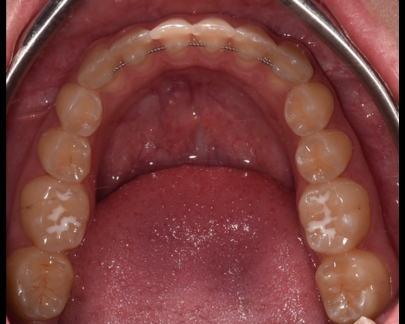

Există două tipuri principale de contenție utilizate în ortodonție: contenție fixă și contenție mobilă.

- Contenția fixă: Acest tip de contenție implică utilizarea unor dispozitive fixate permanent pe dinți.

De obicei, este folosit un fir de sârmă metalică (fir de retenție) care este lipit în spatele dinților,

astfel încât să nu fie vizibil în timpul zâmbetului.

Contenție fixă inferioară |

Contenție fixă superioară |